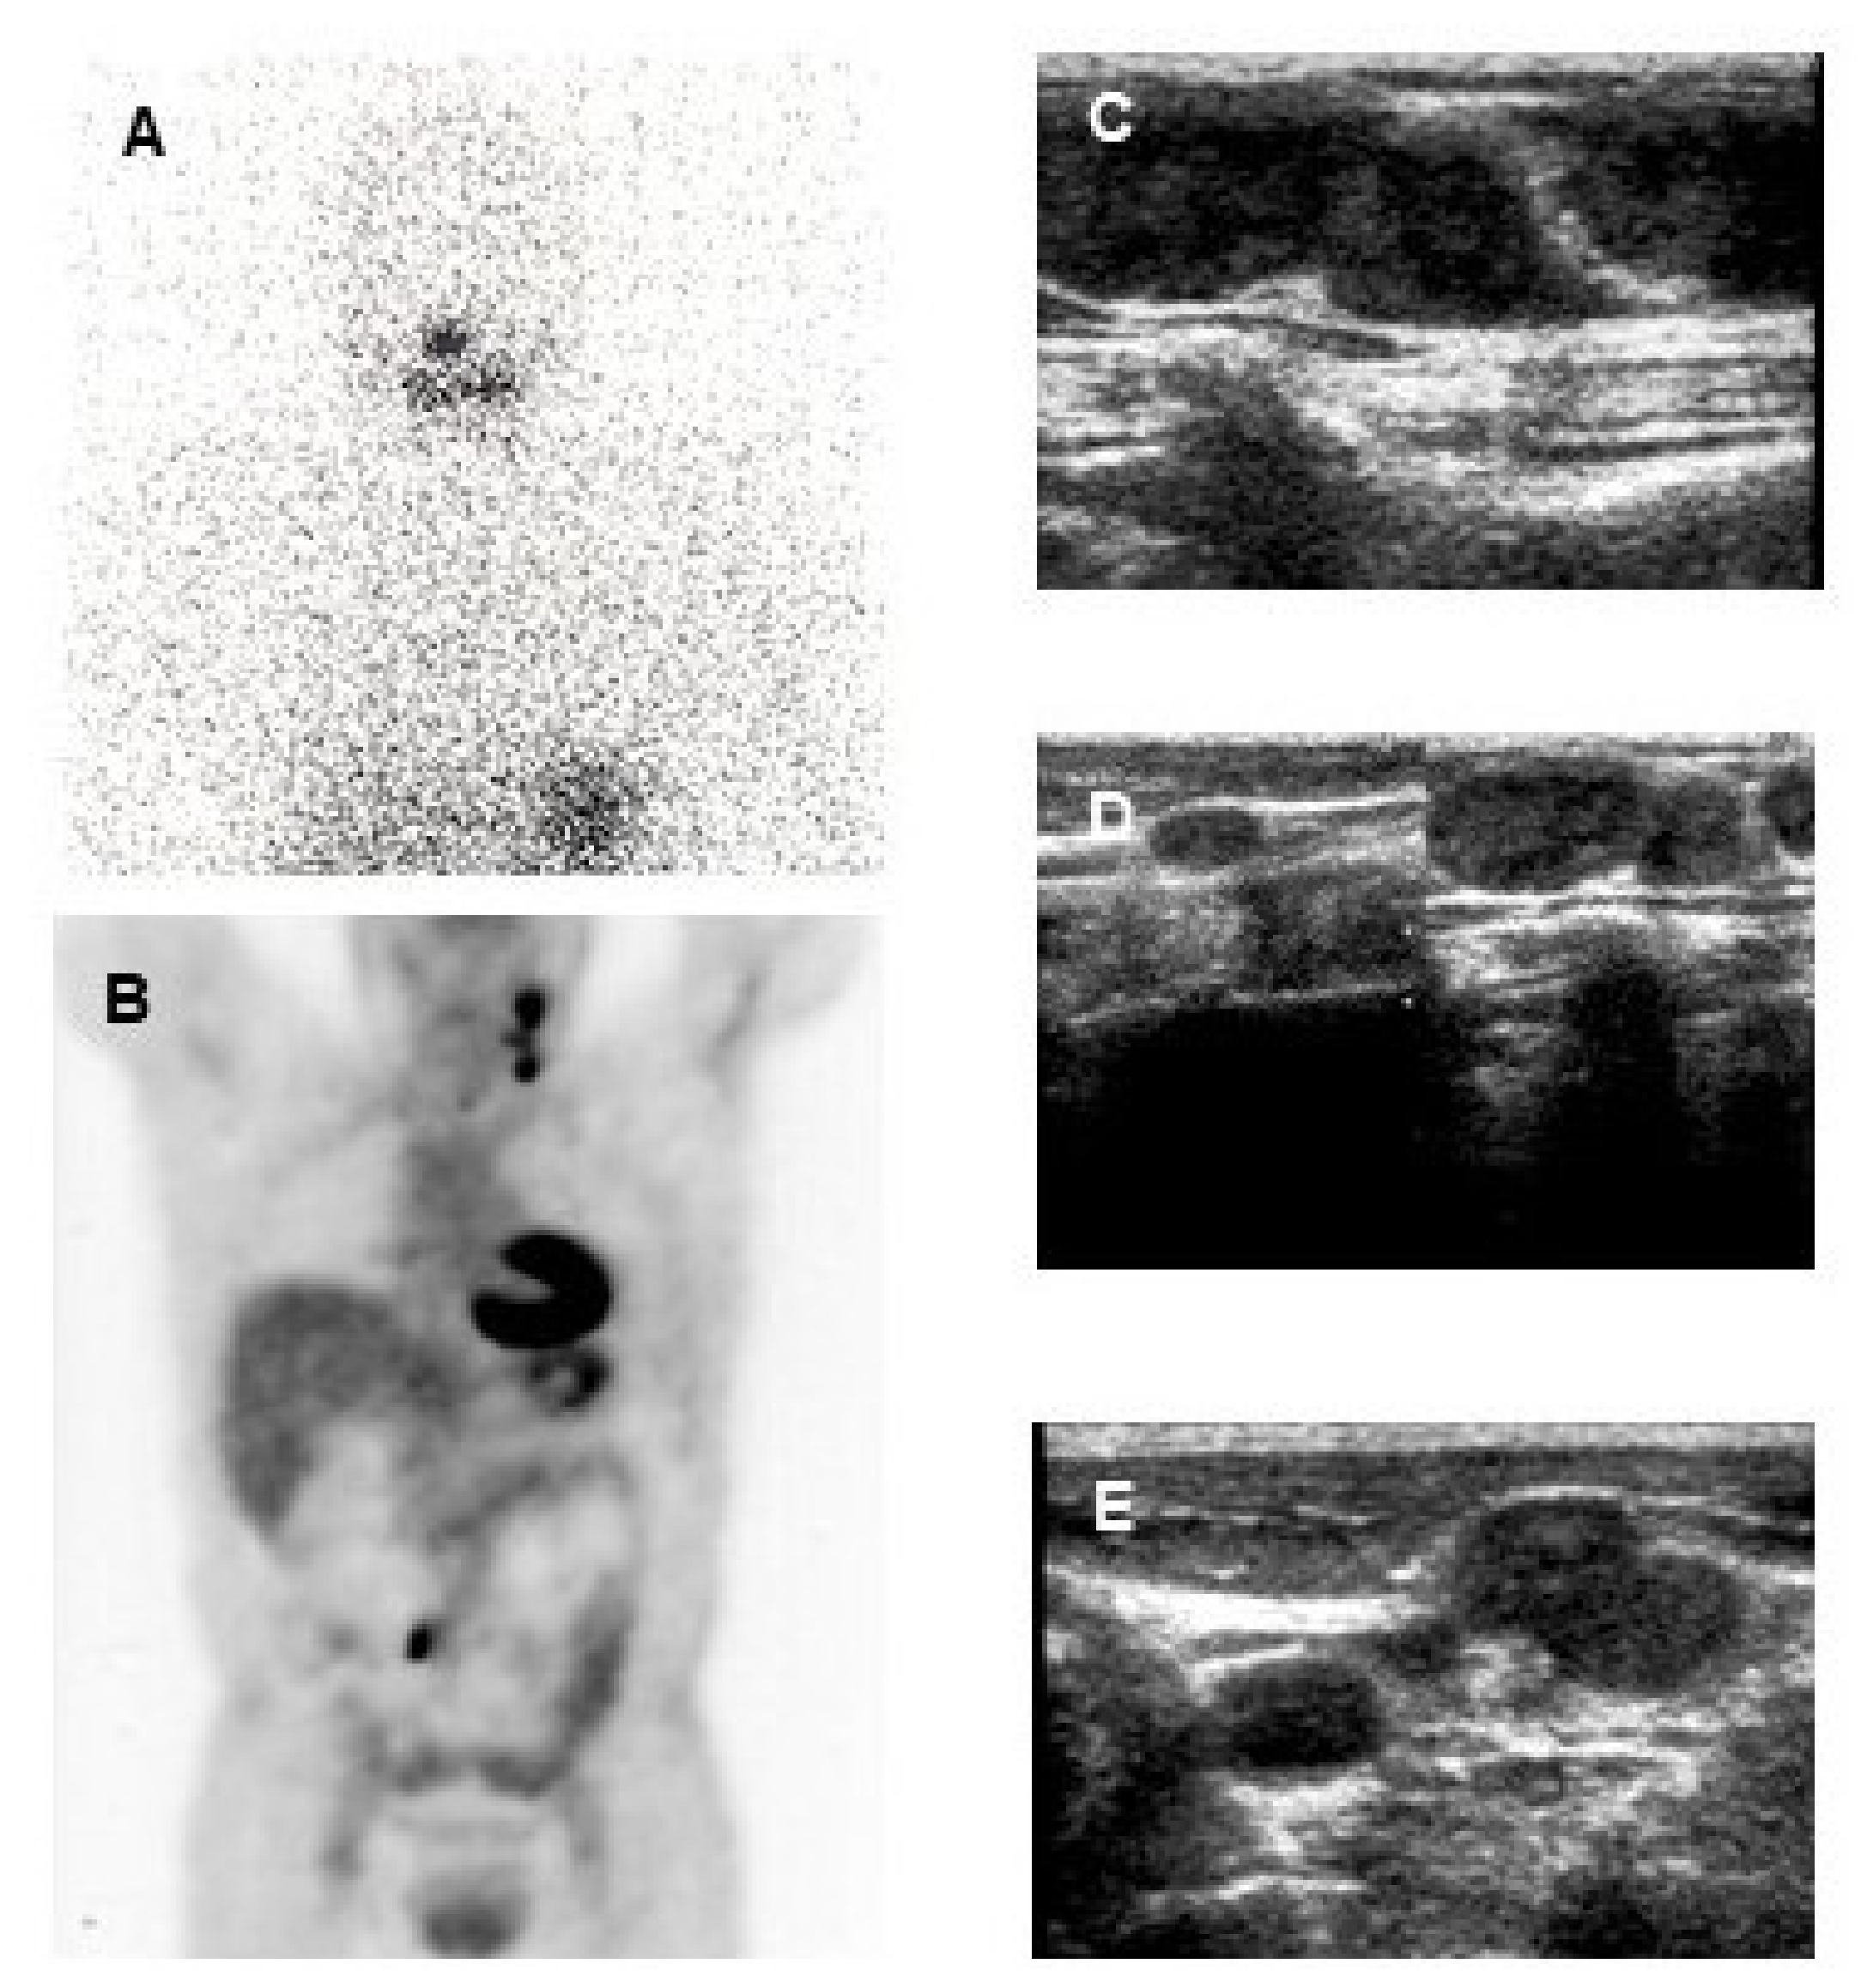

In low-risk patients, retrospective studies did not demonstrate consistent benefits of the post-operative 131I administration in terms of recurrence and mortality [4,9,94,95,96,97,98]. Discrepant results are, at least in part, related to differences in risk assessment: the TNM classification of the risk of cancer related death was used in many studies to predict the risk of recurrence and a retrospective study based on the ATA risk stratification of recurrence did not show any benefit of the post-operative administration of 131I in low-risk patients [98]. This is not surprising given a risk of persistent structural disease after surgery of less than 5% that can be frequently cured with a later treatment and a risk of mortality of less than 1%. Additionally, after total thyroidectomy that normally leaves only small remnants of non-tumoral thyroid tissue, the follow-up can reliably be based on serum Tg determination obtained on thyroid hormone treatment and neck ultrasound, even in the absence of post-operative 131I administration (Figure 5) [4,9].

Figure 5.

37-year-old woman with a papillary thyroid cancer (tall cell variant) with a post-operative TSH-stimulated serum thyroglobulin (Tg) level of 230 ng/mL. Post-therapy 131I whole-body scan (A) did not show any area of increased uptake. 18F-FDG PET-CT (B) evidenced multiple areas of increased uptake in the left latero-cervical region and homogeneous cardiac 18F-FDG uptake (that is not an infrequent finding, also in patients without overt cardiac disease). Ultrasound (C,D,E) evidenced multiple suspicious lymph-nodes in the left latero-cervical region, with round shape, loss of echogenic hilus and micro lobulated margins. At fine needle aspiration cytology confirmed lymph node metastases from the papillary thyroid cancer and the Tg concentration was elevated (3800 ng/mL) in the aspirate fluid.